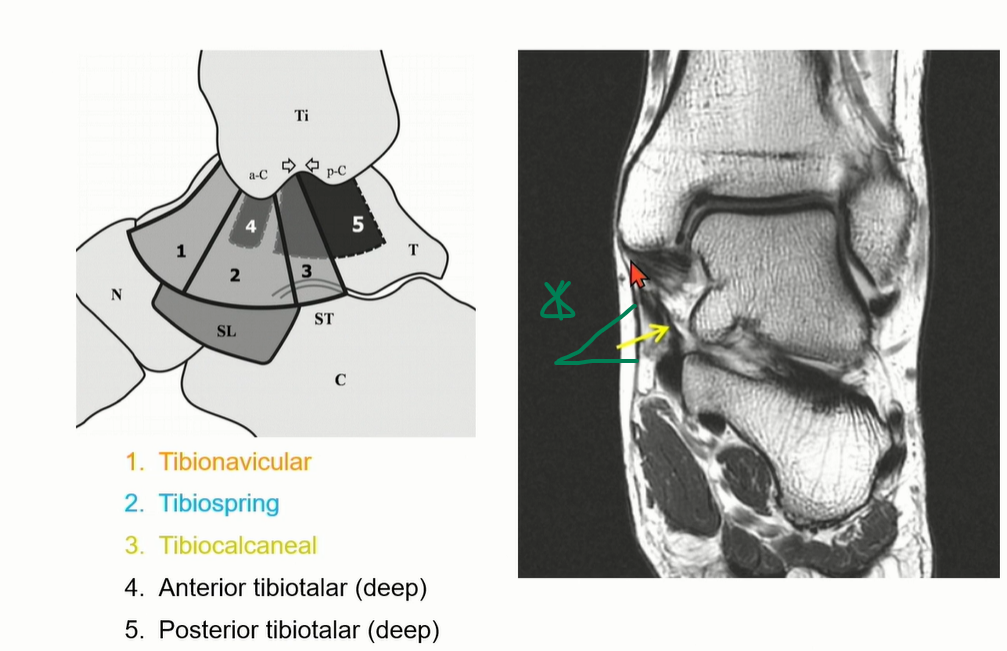

3. Deltoid ligament

Superfical Deltoid ligament: 1-3

Deep Deltoid ligament: 4-5

Superficial은 사실상 연속적인 구조로 되어 있다. 구분은 인위적.

Tibiocalcaneal ligament는 calcaneus의 sustentaculum tali로 이어짐. 비교적 수직으로 주행하기 때문에 관찰 용이.

(Deltoid ligament의 superficial ligament의 3번에 해당)

Tibiospring ligament는 Deltoid ligament의 superficial ligament의 2번에 해당.

spring ligament에 붙는다.

Deltoid ligament의 superficial ligament의 1번에 해당하는 tibionavicular ligement는 주행이 비스듬해서 coronal에서는 잘 관찰이 어렵다. (navicular tuberosity에 붙음)